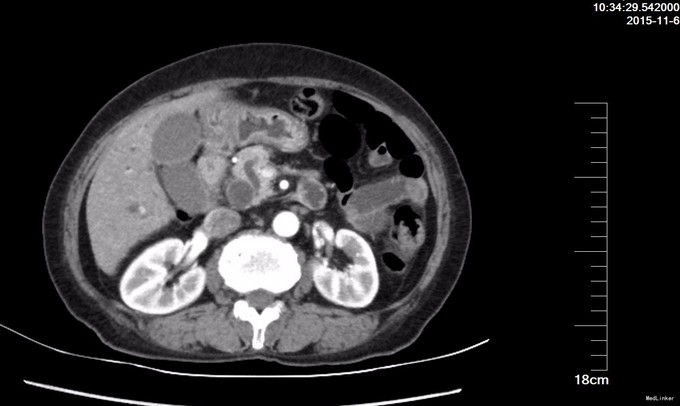

查体: T36.6℃,P78次/分,R16次/分,BP135/75mmHg,全身皮肤及巩膜黄染,无腹壁静脉曲张,未见胃肠型及蠕动波,腹部触之软,无压痛,无反跳痛及肌紧张,肝脾肋下未触及,Murphy's征(-),肝脾肾区无叩痛,移动性浊音(-),肠鸣音4次/分. 辅查: 肝功能化验总胆红素明显升高,以直接胆红素升高为主。 CT提示肝脏大小形态正常,肝内见小囊状不强化灶。肝内外胆管普遍明显扩张,胆总管管径约2.0cm。胆囊增大,肝门部胆管内见高密度结节影,约1.1cm;胰管扩张,约0.8cm,壶腹部见一软组织密度结节影,约1.6cm×1.4cm,增强扫描强化明显不均匀。 EUS:超声探头置于十二指肠球部扫查,见胰管扩张,直径约8mm,胆总管扩张,直径约23mm,胆总管末端见一低回声肿块,内部回声不均匀,大小约23x18mm。

术后复查CT, 胰肠吻合口周围渗出较多,肠壁水肿,肝内胆管多发气体密度影。双侧胸腔可见液性密度影,双肺下叶膨胀不良。术后动态监测引流液淀粉酶,前5天不高,术后7天引流液淀粉酶超过1万,按照2005年国际胰瘘定义研究小组( international study group on pancreatic fistula , ISGPF) 对胰瘘的定义:术后≥3 d 起从手术放置的引流管(或以后放置的引流管或经皮穿刺引流) 中引出淀粉酶大于正常血清淀粉酶水平3 倍的液体且引流量可计,本例属于胰瘘。胰瘘既可以是胰肠吻合口瘘,也可以是来源于胰腺实质的与吻合口无关的渗漏,进一步经引流管造影,发现肠粘膜显影,提示胰肠吻合口瘘。胰瘘分为无临床症状的A级胰瘘,临床相关的B级胰瘘,导致病人腹痛、发热或血中性粒细胞升高,需要使用抗生素、全胃肠外营养(TPN)或生长抑素等治疗,还有威胁生命的C级胰瘘,需要积极使用抗生素、TPN或生长抑素,甚至需要手术或转入重症监护病房,也可能术后死亡,本病例属于最轻的A级胰瘘。胰腺术后总体胰瘘发生率20-40%,胰体尾切除后胰瘘发生率高于胰头切除术后。本例虽发生胰瘘,但是症状轻,最终术后3周愈合,拔管出院。